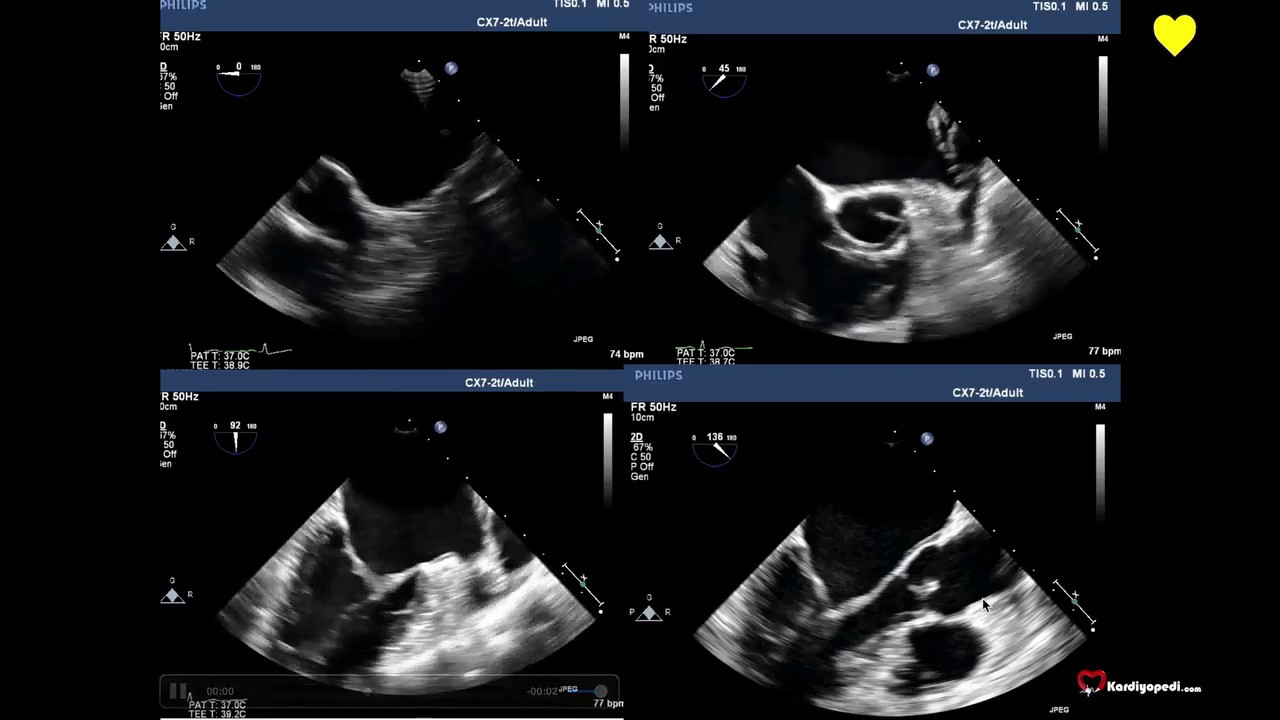

2D Standart Transözofajiyal Ekokardiyografi Pencereleri

2D transözofajiyal ekokardiyografi (TOE), kalbin yapısını ve fonksiyonunu daha ayrıntılı incelemek için kullanılan invaziv bir görüntüleme yöntemidir. Özellikle transtorasik ekokardiyografi ile görüntülenmesi zor olan yapıları değerlendirmek için tercih edilir. Bu teknikte kullanılan temel pencereler, ultrason probunun özofagus içine yerleştirilerek kalbin farklı açılarını ve bölgelerini görüntülemesini sağlar.